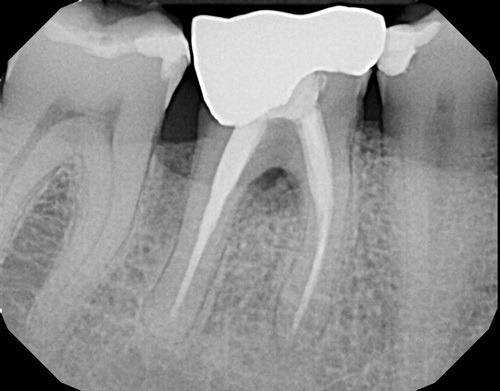

An X-Ray of a lower molar tooth with a root filling, visible as white lines inside the tooth roots.Two root fillings inside a lower molar

An X-Ray of a lower molar tooth with seven root canals.Seven root canals

The image above shows a molar tooth with SEVEN tiny root canals.